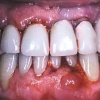

Parodontiit